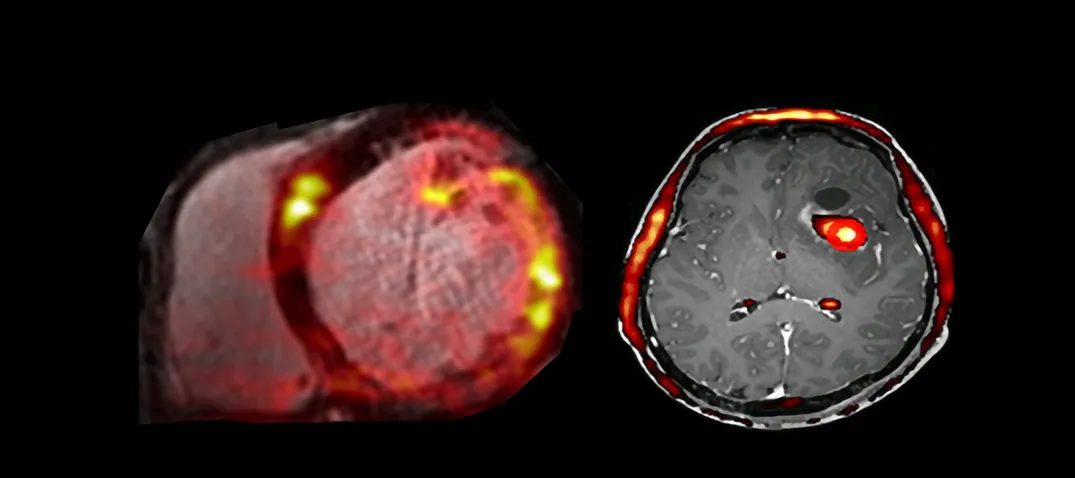

Hybrid radionuclide imaging (PET-MR) is a first year course in the Edinburgh Imaging Academy’s post-graduate PET-MR principles and applications Certificate. It can also be taken not-for-credit as CPD / CME. Image MR scans with PET derived colour overlays. Our online Hybrid radionuclide imaging (PET-MR) (HPMR) course brings together key theoretical and practical information about radiopharmacy, positron emission tomography (PET) and magnetic resonance (MR) imaging. It describes the combined PET-MR technique, and covers issues around patient management. Some clinical and research applications illustrate how PET-MR is implemented. You can download our syllabus, which includes all the learning objectives for each module and lecture, here: Document Edinburgh Imaging Academy - Hybrid Radionuclide Imaging PETMR (582.58 KB / PDF) We offer multiple options for studying Hybrid radionuclide imaging (PET-MR): As a stand-alone course, gaining university credits: Starts in January / Winter / Semester 2 10 university credits As a stand-alone course, without university credits for CPD / CME preparation: Starts anytime Embedded in one of our online degree programmes: PET-MR principles & applications Cert We asked Dr Adriana Tavares, Research Fellow in PET Imaging & main tutor for the Hybrid radionuclide imaging (PET-MR) course, to describe the course in more detail: Who is the HPMR course aimed at? This course is aimed at colleagues working in the field of medical imaging either in the clinic or in the research context who seek to learn more about PET and MR imaging. The course materials can also be valuable assets to undergraduate and post-graduate students wanting to learn more about PET-MR imaging to support their studies as well as boost their professional development and knowledge level. What can you learn in the HPMR course? The course covers basic theoretical concepts in PET imaging as well as practical aspects of conducting PET-MR studies. It also covers fundamentals of PET radiotracer production, general PET physics, including acquisition and reconstruction principles. Quality control methods routinely used in PET departments are reviewed alongside practical aspects of PET-MR imaging. What benefits can you get from our online study options? Online study options can provide the student with excellent flexibility to learn new and exciting topics remotely. The PET-MR course was designed to convey important knowledge via online pre-recorded lectures while maintaining a close link between student and tutor via the course active forum. What outcomes / what can you expect at the end of the HPMR course? At the end of the course you can expect to have a wider understanding of PET-MR techniques, ranging from fundamental PET physics to radiochemistry and practical considerations on MR safety. Relevant links Hybrid radionuclide imaging (PET-MR) Edinburgh Imaging Academy Short courses Degree programmes Training tools About our students What is a PET-MR scan? What is a PET scan? What is a MR scan? In the news: 27 Jan 22. Online learning: Study design 15 Dec 21. Online learning: Practicalities & safety 06 Dec 21. EIA January admissions 29 Nov 21. Online learning: Anatomy (body) 27 Oct 21. Online learning: Anatomy (neuroanatomy) 27 Sep 21. Online learning: Statistics 15 Sep 21. National Online Learning Day 27 Aug 21. Online learning: Clinical applications 27 Aug 21. Online learning: Applications in disease 27 Jul 21. Online learning: Techniques & physics 18 Jun 21. PET-MR neuroimaging course 15 May 21. New cardiac imaging educational resource 11 May 21. ACTATS one year on 21 Dec 20. Tutor of the Month 13 Aug 20. ACTATS milestone 07 May 20. ACTATS goes live 25 Nov 19. Edinburgh Imaging Academy graduations Social media tags and titles Hybrid radionuclide imaging (PET-MR) is a first year course in the Edinburgh Imaging Academy’s post-graduate PET-MR principles and applications Cert. It can also be taken not-for-credit as CPD / CME. @EdinUniMedicine @uoe_online Publication date 20 Jan, 2022